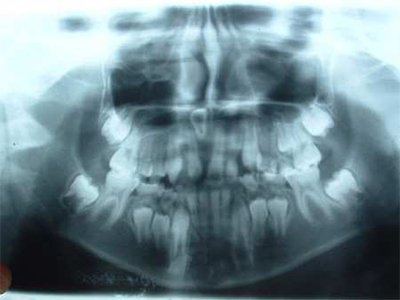

8岁儿童牙齿x光片

8岁儿童牙齿x光片,4岁儿童牙齿x光片

4岁儿童牙齿x光片

儿童牙齿x光片

儿童换牙前x光片